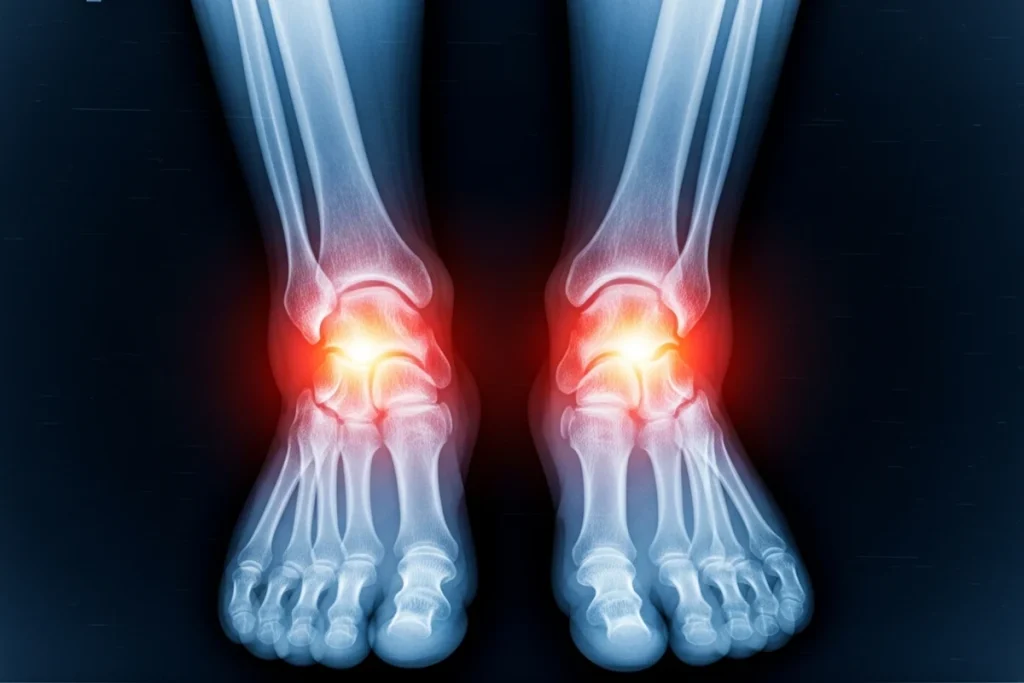

RA is a long-term disease where your immune system attacks your own joints by mistake. In your feet, this causes swelling, pain, stiffness, and over time, it can wear down joint tissues. When RA hits the feet, even small movements may hurt, and walking can become difficult. If you experience any of the signs and symptoms below, you will need to get rheumatoid arthritis treatment in Gilbert.

You may notice symptoms like joint pain, swelling, stiffness, warmth, and trouble moving your toes or ankles. Sometimes your feet may feel “off,” or joints seem to shift out of place.